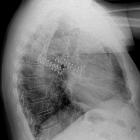

Rippenklammern

Osteosynthese

bei instabilem Thorax bei Rippenserienfraktur mit Rippenklammern.

instabile Brustwand Rippenklammern. Neben den versorgten Rippenfrakturen beidseits weitere weniger verschobene Frakturen.